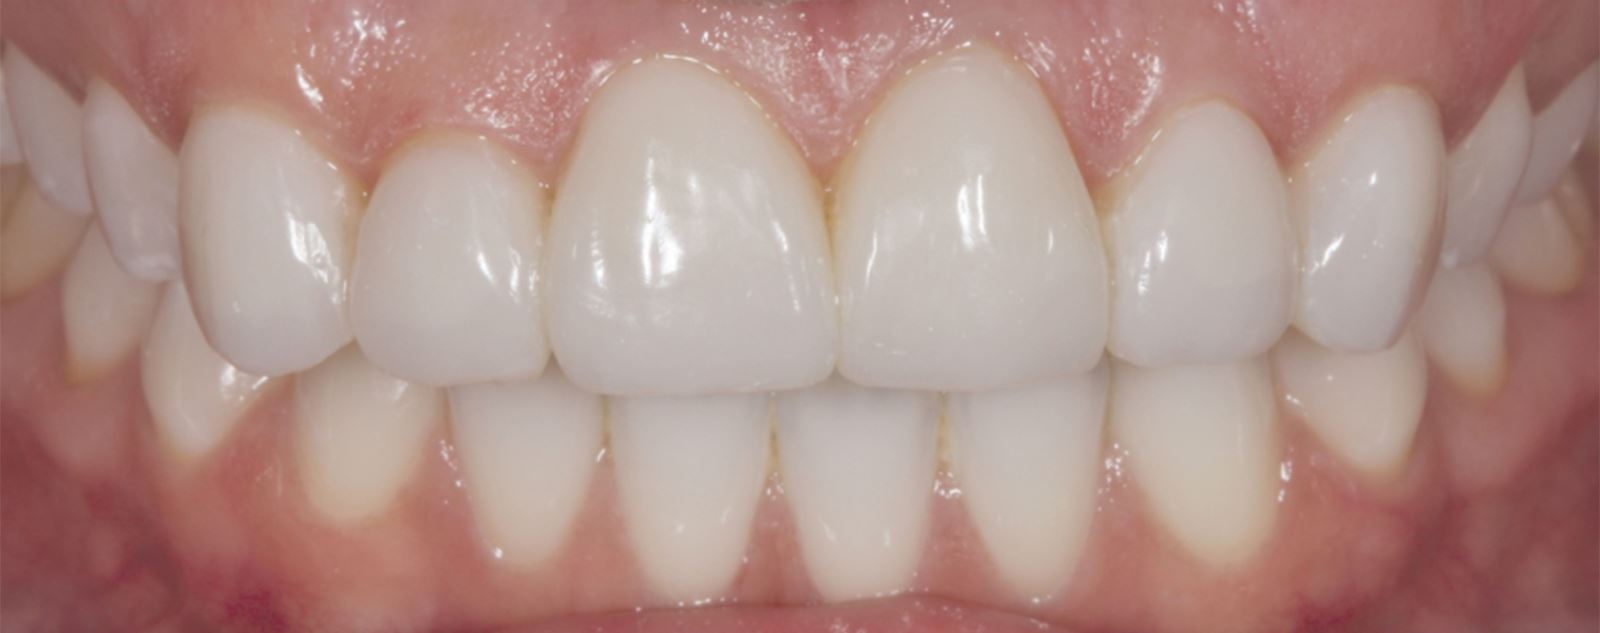

Výsledok a záverečné zhodnotenie

Tento postup úspešne vyriešil estetické obavy pacientky prekrytím diskolorácie horných frontálnych zubov a dosiahnutím prirodzeného, vyváženého vzhľadu vo vzťahu k dolným frontom. Použitie kompozitných faziet bez preparácie poskytlo konzervatívne, vysoko efektívne riešenie, ktoré rešpektovalo finančné možnosti pacientky a jej požiadavku na minimálne invazívny prístup.